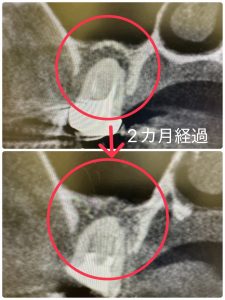

とにかく根管治療病巣が多い😭

良く治癒に近づいてる💪

如何に早く骨化させるか!が、直近のテーマ